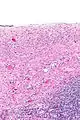

Histopatología

Los cistoadenomas serosos se diagnostican mediante examen histomorfológico, por patólogos. En general, son quistes uniloculares que contienen un líquido claro de color pajizo. Microscópicamente, el revestimiento del quiste consiste en un epitelio simple con cilios que puede ser columnar o plano.